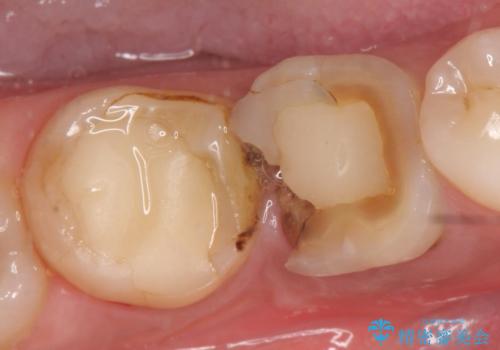

- 奥歯が欠けてしまったので診て欲しいといらっしゃった方の症例です。

再根管治療終了後、オールセラミッククラウンによる補綴を行いました。